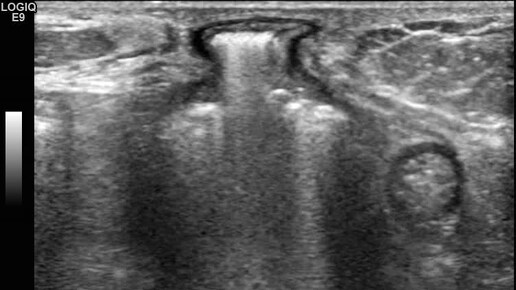

Видео к статье "Общие принципы ультразвуковой диагностики наружных грыж живота" Адрес: https://dzen.ru/a/Z2k58ScRsjQP-dA9